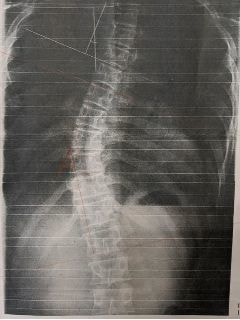

レントゲンのビフォーアフター)

写真1(施術前) 写真2(5か月後)

○コブ角上27度⇒25度(2度改善)、下40度⇒33度(7度改善)

※コブ角は専門医の診断

施術19回:コブ角33度

施術前:コブ角40度